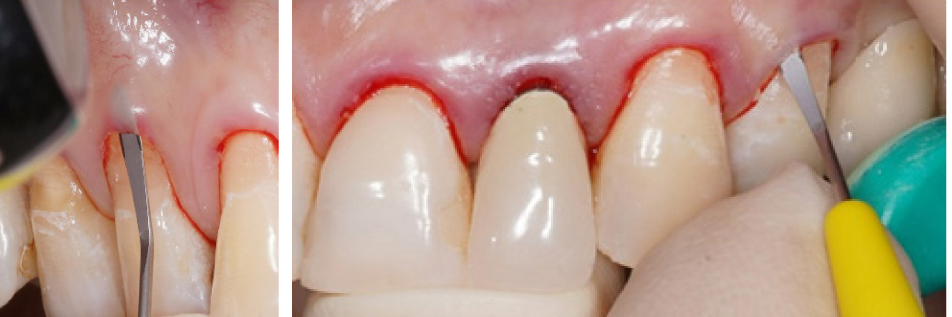

Вначале проводилась антисептическая обработка полости рта 0,05%-м раствором хлоргексидина биглюконата, аппликационная и инфильтрационная анестезии. Затем выполнялись разрезы в области десневой борозды (сулькулярные) через каждую зону рецессии микрохирургическим лезвием с сохранением кончиков десневых сосочков (рис. 2), отслаивание полнослойных лоскутов с помощью микрохирургического распатора. Далее производился забор свободного десневого трансплантата с неба с последующей его внеротовой деэпителизацией и наложением на зону забора параллельных и перекрестных горизонтальных обвивных швов (рис. 3). Позиционирование и фиксация трансплантата в принимающем ложе, ушивание раневой поверхности швами Аллена (рис. 4). Даны рекомендации по послеоперационному ведению: полоскания 0,05%-м раствором хлоргексидина биглюконата 2 раза в день в течение 2 недель, назначены противовоспалительные и обезболивающие лекарственные препараты (НПВС). Повторная явка через день. Швы снимались на 7–10-е сутки. Контрольные осмотры проводились через 3 и 6 месяцев, 1, 2 и 3 года соответственно, оценивалось состояние мягких тканей в области хирургического вмешательства и степень закрытия рецессий десневого края.

Рис. 3. Забор свободного десневого трансплантата с нёба (а) и его деэпителизация (б)

Рис. 4. Наложение швов Аллена